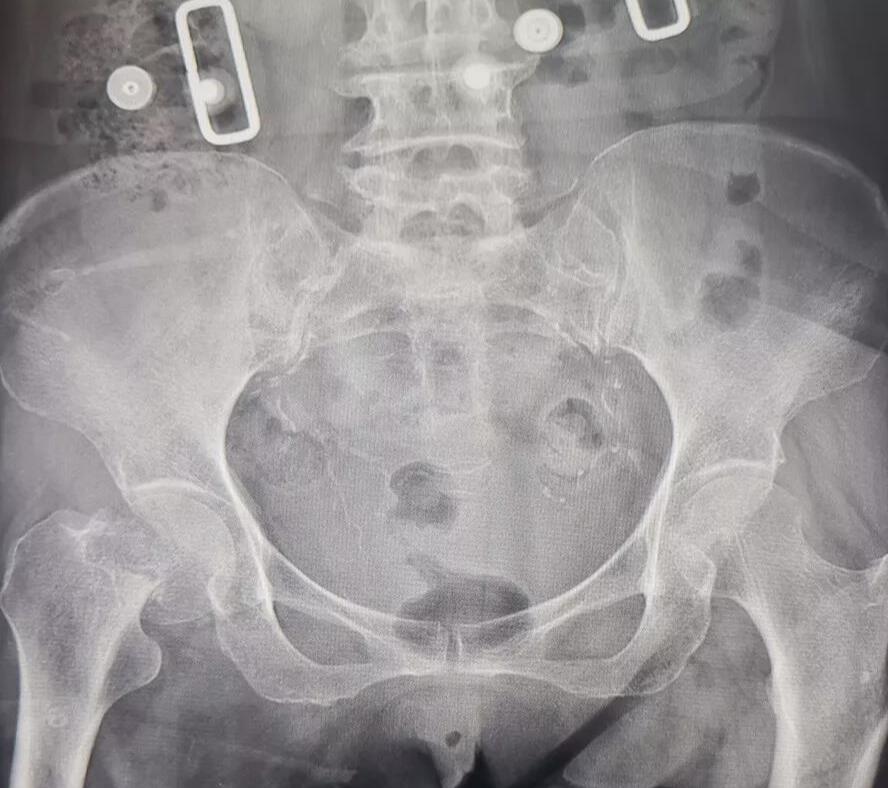

7月4日,我院接收了一名右髖部摔傷患者,此患者進(jìn)院時(shí)活動(dòng)受限,臥床難起,再加上此患者平素身體素質(zhì)很差,患有糖尿病20余年、患有冠心病8年、患腦梗塞7年、患高血壓5年,多種并發(fā)癥纏繞,進(jìn)院時(shí)神志淡漠,精神比較差。在經(jīng)過(guò)檢查和了解患者情況之后,擬以“右側(cè)股骨頸骨折”收住入院。

醫(yī)生在詳細(xì)了解了病人情況之后與醫(yī)院專(zhuān)家及醫(yī)護(hù)人員對(duì)病情進(jìn)行了深入研究,及時(shí)為患者制定了合理有效的治療方案。在與家屬溝通確定之后對(duì)患者進(jìn)行了半髖置換手術(shù),由于此患者的病情復(fù)雜,此手術(shù)風(fēng)險(xiǎn)比較大,手術(shù)難度也比較高。